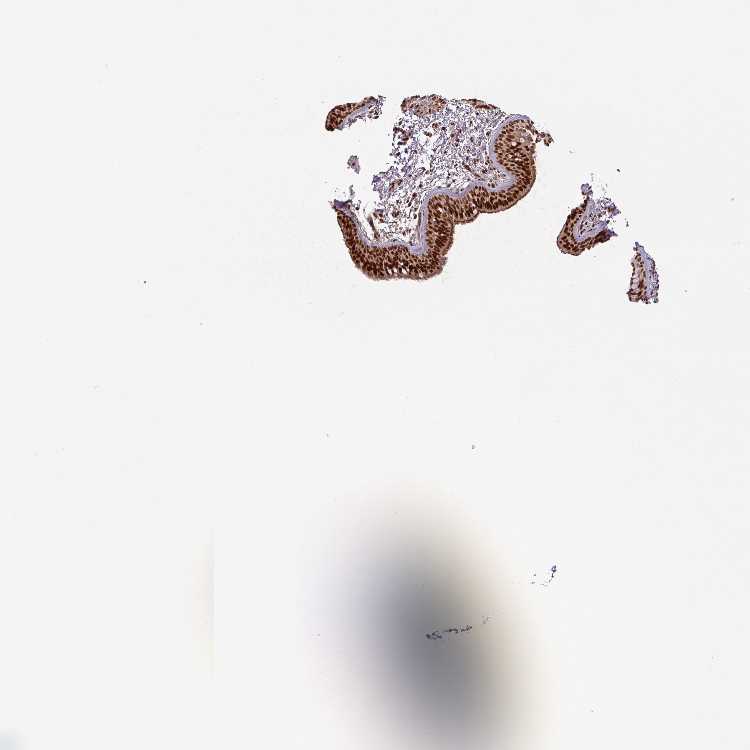

SOFT TISSUE 1 - Antibody stainingi

Antibody staining in the annotated cell types in the current human tissue is reported as not detected, low, medium, or high, based on conventional immunohistochemistry profiling in selected tissues. This score is based on the combination of the staining intensity and fraction of stained cells.

Each image is clickable and will lead to virtual microscopy that enables deeper exploration of all samples and also displays staining intensity scores, fraction scores and subcellular localization as well as patient and tissue information for each sample.

Antibody HPA049905

Fibroblasts High